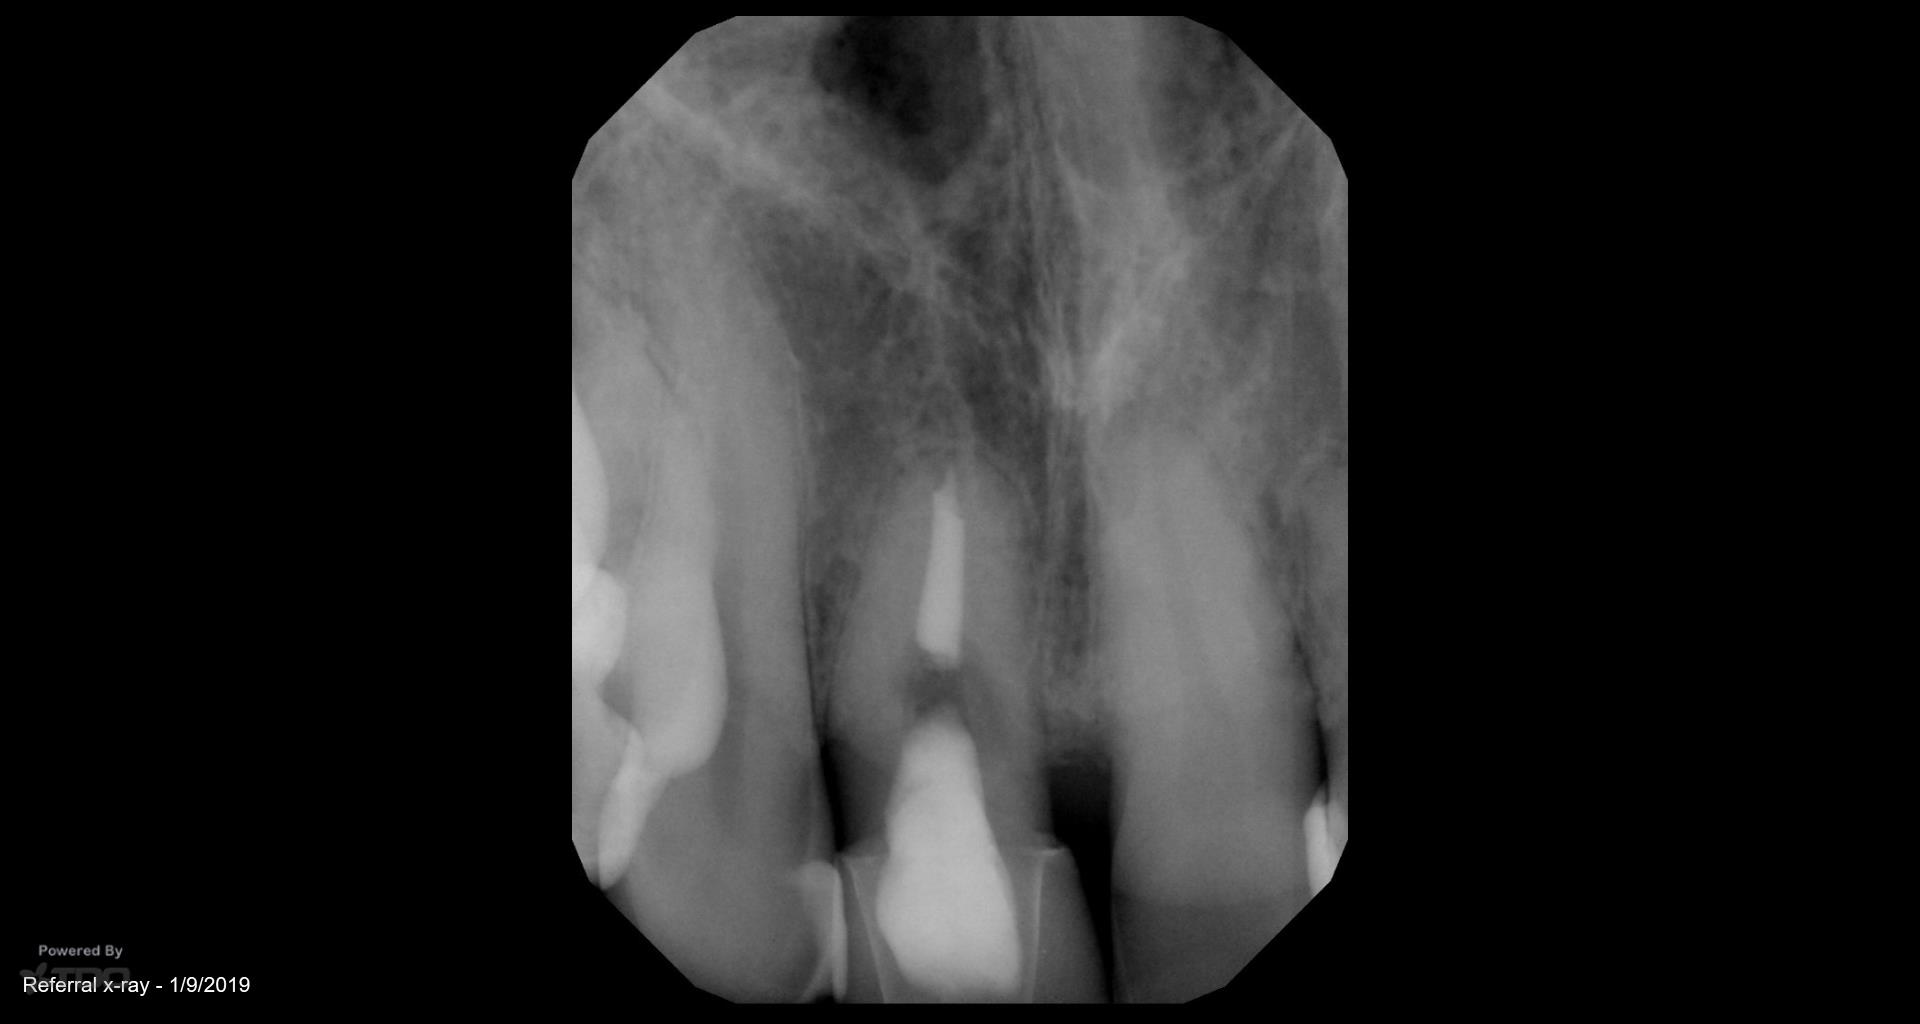

I did this RCT 34 years ago when the patient was 14. Now there is a parulis and lingual palpation sensitivity. Extract or treat? Patient has a very high smile line, thin biotype, is sensitive to costs. gbc